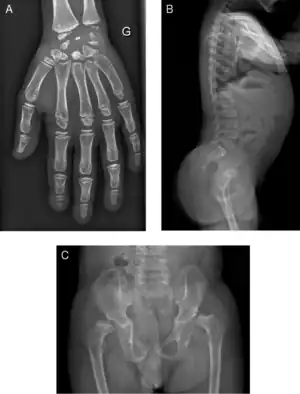

| Radiograph of a WRS child presenting with dysplastic bone growth in various regions of the body. | |

Initially, patients with neonatal or early-childhood onset diabetes are possible candidates for having Wolcott–Rallison syndrome.[1] The other features include multiple epiphyseal dysplasia, osteopenia, intellectual disability, and hepatic and renal dysfunction.[1] Patients having features that suggest Wolcott–Rallison syndrome can be referred for genetics testing. The key way to test for this disease is through genetic testing for EIKF2AK3 mutations.[7] Molecular genetic analysis can be done for the patient and the parents to test for inherited or de novo mutations. It can also show whether the patient's parents are heterozygotes or homozygotes for the normal genotype.[4] X-rays can show bone age in relation to actual age. In typical WRS patients the bone age is a few years less than the chronological age.[4][5][8][9] Hypothyroidism is rare in WRS patients but can occur.[4]